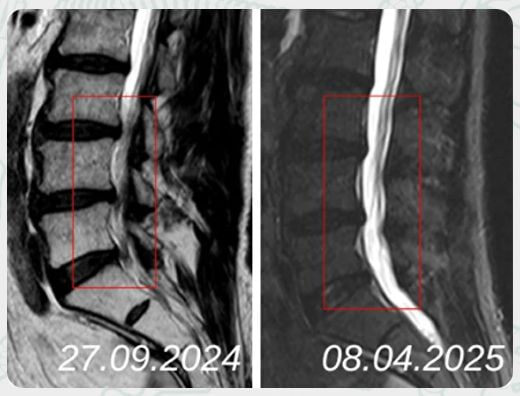

Вылечить грыжу позвоночника можно без операции! Резорбция межпозвонковой грыжи - естественный процесс для организма, физиологический процесс, в ходе которого происходит рассасывание грыжевого выпячивания с последующим формированием рубца.

Процесс естественной резорбции происходит либо длительное время — около 12 месяцев, либо может не произойти совсем.

Лечение межпозвоночной грыжи методом моделируемой резорбции воспринимается врачебным сообществом как один из перспективных методов лечения регенеративной медицины. Процесс естественной резорбции может занимать от 3 месяцев, при сложных случаях дольше.